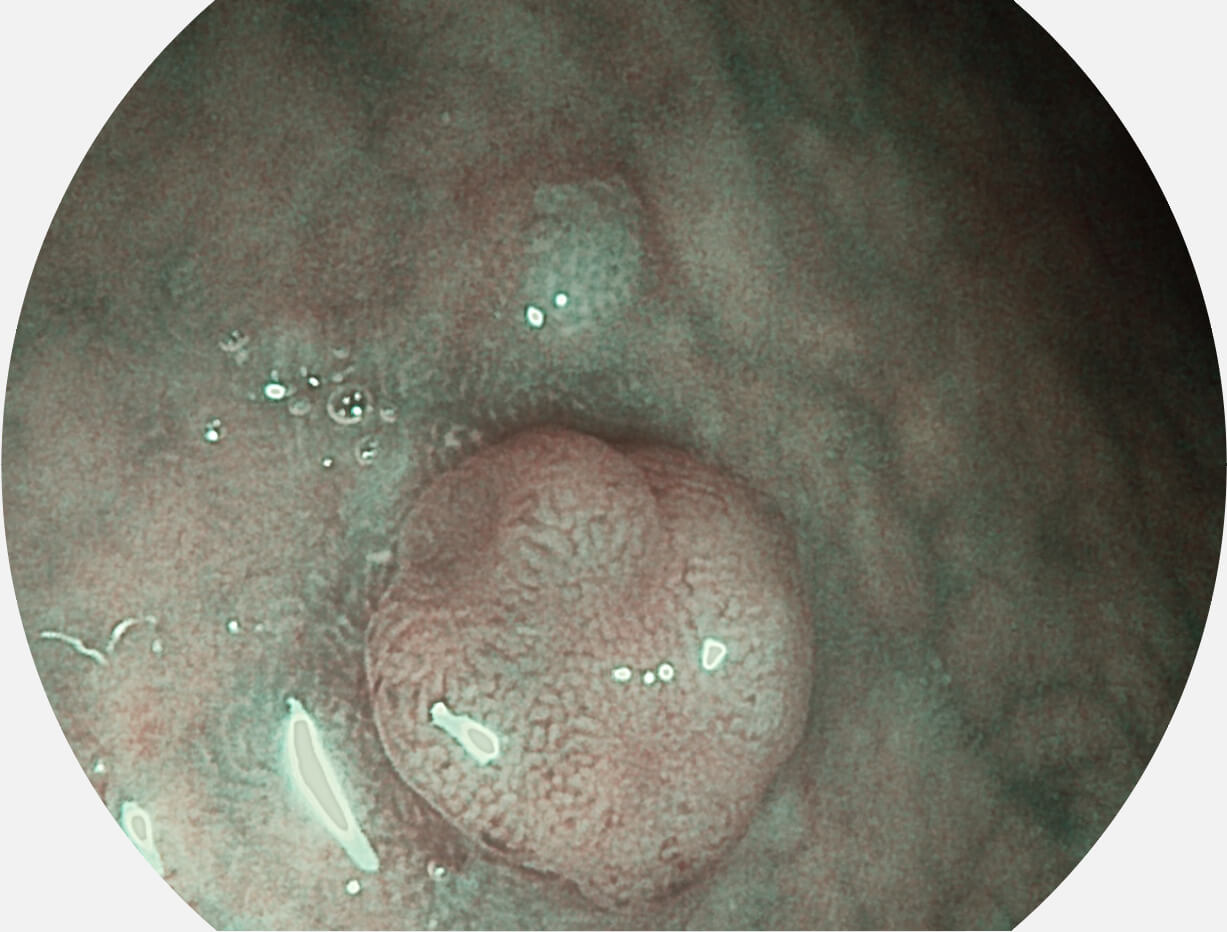

Spectral Focused lmaging, SFI

图像具有高亮度、高黏膜血管颜色对比度的特点,且不改变粘液、食物残渣、粪便的基本颜色,可在中远景下进行观察,助力消化道早期疾病的诊断。

SFI图像

白光图像